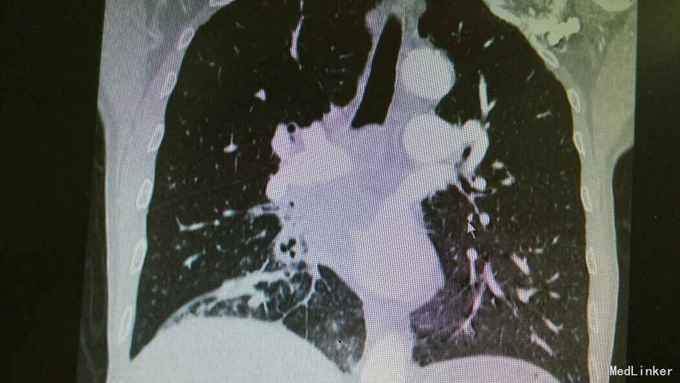

主诉:活动后气促,胸闷1年,消瘦8月余。 病史:患者1年前无明显诱因出现活动后气促,胸闷,主要为胸骨段,爬坡可诱发,伴有咳嗽,白色粘痰。伴有体重下降。

查体:慢性病容,桶状胸,双肺呼吸音粗,右下肺可闻及少量细湿罗音。 辅查:胸部CT:考虑右下肺中央型肺癌并癌性空洞形成,右下肺阻塞性肺炎 ,右下肺动静脉受累,纵隔,双侧肺门多发淋巴结肿大。

诊断:中央型肺癌并阻塞性肺炎。 治疗:入院予以抗感染,止咳化痰等治疗。